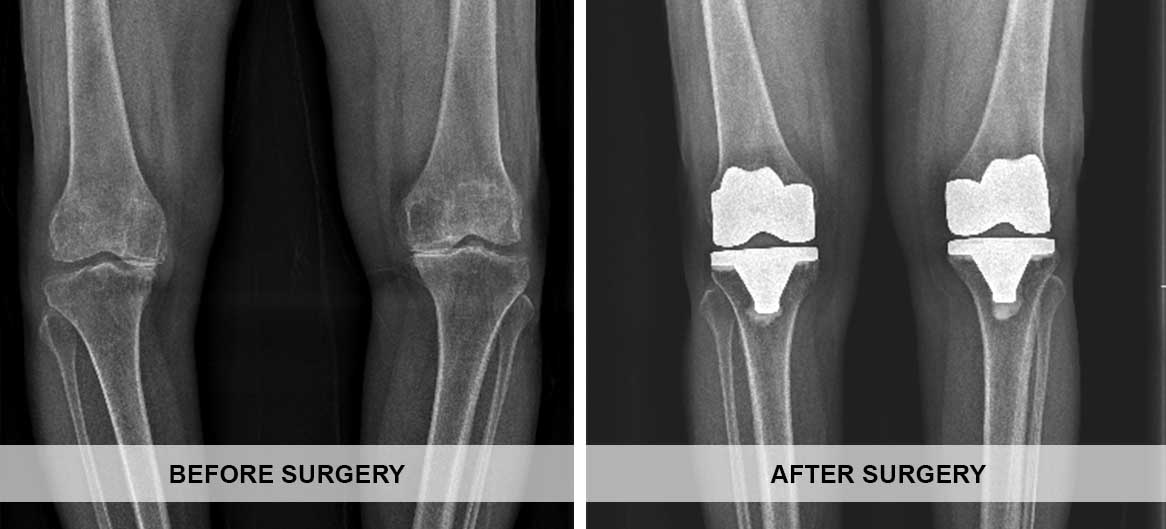

Total Knee replacement